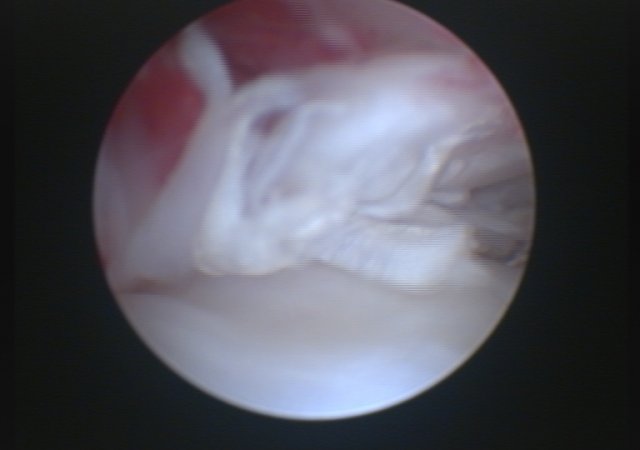

In unserer Praxis bieten wir mit der Arthroskopie die minimalinvasive Möglichkeit auch Anrisse des vorderen Kreuzbandes sicher zu diagnostizieren und gleichzeitig den häufig mitbetroffenen Meniskus zu untersuchen und zu operieren.

Arthroskopie gerissenes Kreuzband

Arthroskopie Meniskus Nahaufnahme

Arthroskopie Meniskus